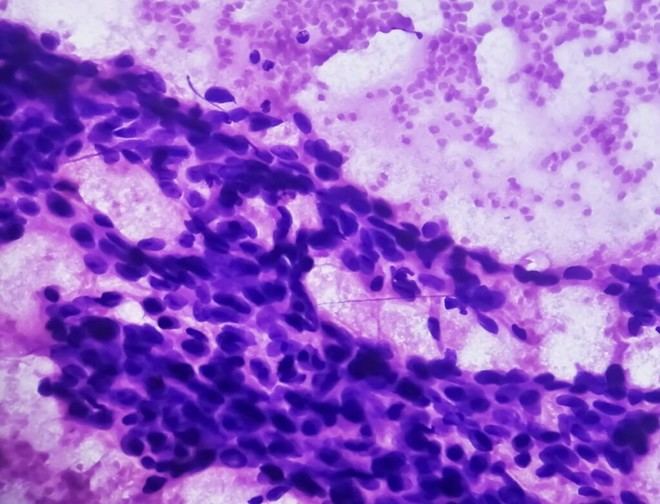

El proyecto, liderado por la empresa Nanoligent, cuenta con el respaldo de un consorcio que combina esfuerzos públicos y privados. Su objetivo principal es desarrollar una estrategia terapéutica innovadora basada en nanomedicina para tratar tumores sólidos avanzados. Esta estrategia se centra en la eliminación selectiva de células tumorales que sobreexpresan el receptor CXCR4, una proteína asociada a la agresividad y diseminación del cáncer.

La meta es avanzar hacia la fase preclínica regulatoria, donde se busca liberar compuestos citotóxicos específicamente en aquellas células que exhiben altos niveles de CXCR4. De esta manera, se pretende atacar el tumor sin causar daño a los tejidos sanos circundantes.